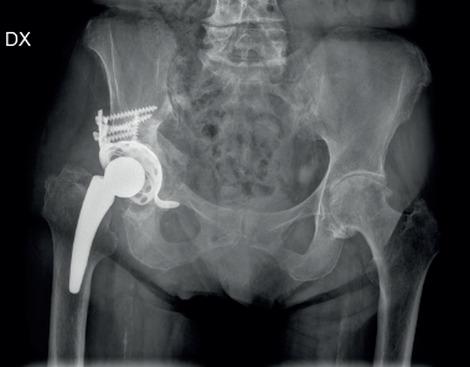

The implantation of short femoral stems has significantly increased over the past decade, thanks to their preservation of bone stock, allowing for easier potential revision of components and physiological joint reconstruction. Their main features are metaphyseal fixation and partial retention of the femoral neck which lead to biomechanical advantages and high stability. They also guarantee the preservation of bone stock and insertion through minimally invasive approaches. Fifty-one non-consecutive patients with osteoarthritis or avascular necrosis were treated by two senior surgeons with total hip arthroplasty (THA) with anterior or anterolateral approach between April 2013 and October 2016. Cementless short femoral stem monobloc (Minihip, Corin, Cirencester, UK) was implanted in all patients who were studied retrospectively. Radiographic outcome was analyzed and clinical outcomes were assessed with Harris Hip Score (HHS), Hip handicap and Osteaorthritis Outcome Score (HOOS) and Oxford Hip Score (OHS). Based on radiological results we did not find periprosthetic osteolysis while bone resorption was evaluated in 5 implants which were classified according to Gruen. The MiniHip stem demonstrates adequate metaphyseal grip, excellent implant stability to ensure implant survival.

在过去十年中,由于短股骨柄可保留骨量,便于对部件进行潜在的翻修和实现生理性关节重建,因此其应用显著增加。其主要特点是干骺端固定和部分保留股骨颈,这带来了生物力学优势和高稳定性。它们还保证了微创入路的骨量和植入的保留。2013 年 4 月至 2016 年 10 月,两位资深外科医生采用前路或前外侧入路对 51 例非连续的骨关节炎或缺血性坏死患者进行了全髋关节置换术(THA)治疗。所有患者均植入非骨水泥短股骨柄单体(英国科林公司的 Minihip),并进行回顾性研究。分析影像学结果,采用 Harris 髋关节评分(HHS)、髋关节残疾和骨关节炎结果评分(HOOS)和牛津髋关节评分(OHS)评估临床结果。根据影像学结果,我们未发现假体周围骨溶解,而对 5 个根据 Gruen 分类的假体进行了骨吸收评估。MiniHip 柄具有足够的干骺端抓握力,植入物稳定性极佳,可确保植入物的存活。